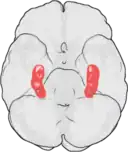

Hippocampus

Hippocampus er en region i hjernen i den mediale tindingelap. Navnet kommer af den kurvede form der til en vis grad ligner en søhest (hvis betegnelse på latin er hippocampus).

Mennesket har to hippocampi, en på hver side af hjernen. Hippocampus er en del af det limbiske system og spiller en rolle i menneskets orienteringsevne og hukommelse.